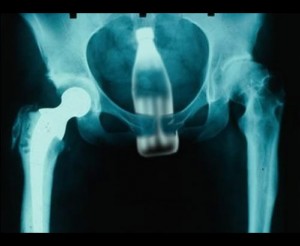

ბოთლი

9 (1)